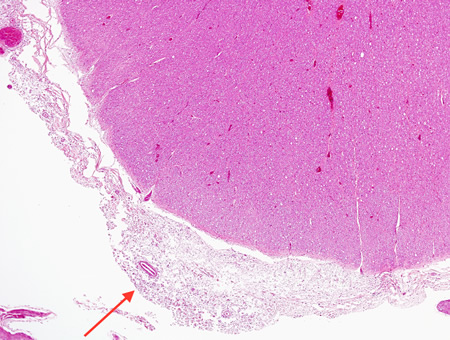

Biópsia do cérebro de paciente imunocomprometido com meningite criptocócica sob baixa magnificação. As meninges estão expandidas (seta), mas o córtex está relativamente não envolvido histologicamente

Do acervo pessoal de Robert E. Schmidt; usado com permissão